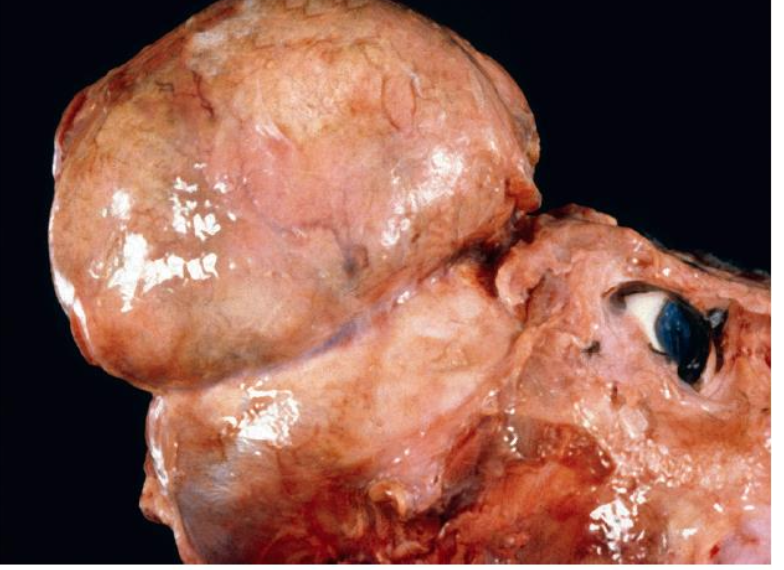

What has occurred in this canine tibia and fibula? note the dog also had an intrathoracic mass.

hypertrophic osteopathy